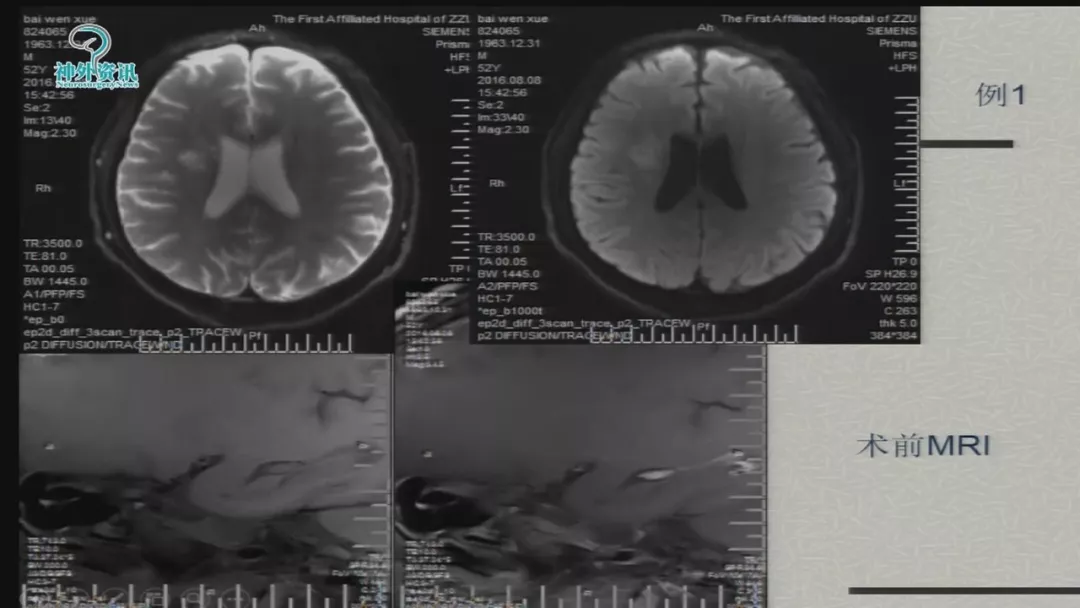

徐浩文:Neuroform EZ在ICAS治疗中的应用丨第七届全国介入医学工程大会精彩回顾

今天为大家分享的是由郑大一附院徐浩文教授在第七届全国介入医学工程大会上带来的“Neuroform EZ在ICAD治疗中的应用”精彩讲课视频和PPT,欢迎观看!(内容未经讲者审核,不当之处请与我们联系)